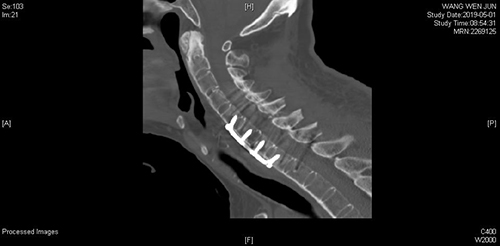

一切准备就绪后,脊柱外科专家们为患者实施了颈椎前后联合入路减压植骨融合内固定术。手术在患者全身麻醉后紧张有序地进行。强直性脊柱炎骨折脱位的患者,脊柱僵硬,由于骨质疏松,无法进行牵引下复位,且常规的侧块螺钉由于把持力小,也难以复位。专家团队首先从后路应用了难度较大椎弓根螺钉进行固定,顺利提拉复位,完成了解剖复位。解剖复位之后,改变患者体位,进行前路手术,在颈6-7椎间进行植骨融合,钛板固定。

手术前后影像学对照(术前C6双侧椎板骨折、C7椎体完全骨折脱位,术后达到解剖复位)

前后路联合手术,使患者颈椎的稳定性大大增加,术后早期就可以下地行走。经过全程监护和系统治疗,患者术后恢复良好,骨折解剖复位,复查X线及CT显示固定位置佳,术后3天即下地行走,术后4天即出院回家休养。